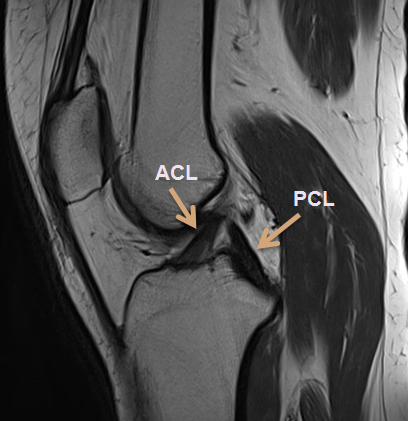

Normal ACL (Anterior Cruciate Ligament) and PCL (Posterior Cruciate Ligament)